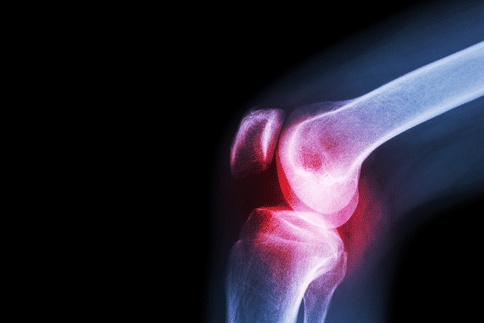

痛风是一种非常常见的疾病,相信很多人都听说过,但是目前的痛风治疗方法较为有限,尤其是国内的医疗技能较差,往往不能取得较好的效果。在这个背景下,美国发表的一项新研究中发现了痛风治疗的新靶标,对于痛风新型治疗方法的出现或有重要帮助。未来,痛风患者或许可以选择出国看病。

在近期发表的一项研究中,来自华盛顿州立大学等机构研究人员揭示了痛风的新治疗靶标。他们的研究发表在《Cellular Molecular Immunology》杂志上。研究指出,通过对叫做“TAJ1”的信号分子的阻断可以有效抑制痛风引起的炎症,这对于后续治疗策略的开发具有关键作用。

研究人员在确定TAK1对于IL-1-beta活性调节具有重要作用的基础上设计了本次研究,从而确定MSU晶体产生IL-1-β炎症的分子机制以及TAK1在这个过程中起到了什么作用。随后研究人员发现在健康的人类巨噬细胞及痛风啮齿动物模型中使用抑制或阻断TAK1的化学物质可以抑制MSU晶体引起的任何炎症。

目前研究人员正在通过对Anakinra方法的临床试验来帮助治疗痛风,但是这种药物尚未应用于临床,且作用有效,长期使用可能会带来感染。因此TAK1抑制剂的开发十分关键,其可以帮助痛风患者控制疾病的发生。